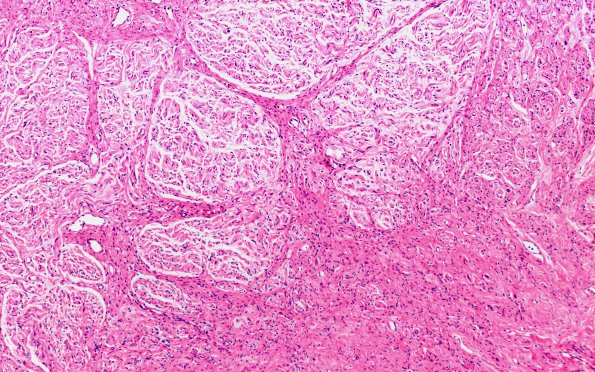

Washington University Experience | PERIPHERAL NEUROPATHY | 19 TRAUMATIC INJURIES | 4A1 Neuroma, traumatic (Case 4) H&E 10X 1

Case 4 History ---- The patient is a 4-month-old full-term male who was delivered via head presentation vaginally and suffered left brachial plexus palsy with persistent weakness in the deltoid, biceps and wrist. No forceps or suction was used to assist with delivery. His birth weight was 11 pounds 1 ounce. He did suffer meconium aspiration. He was placed on a ventilator and transferred to the Arkansas Children's NICU. He required a ventilator for four weeks and was in the NICU for six weeks. His left arm was completely flaccid. There was no evidence of fracture of the clavicle or arm. He did have findings on MRI scan suggestive of potential avulsion at C8. Surgery was performed to remove scar tissue. He was discharged from the hospital after six weeks and began to improve. ---- 4A1,2 In this case many of the nerve fascicles are cut in cross section and are surrounded by mini-fascicles. (H&E)